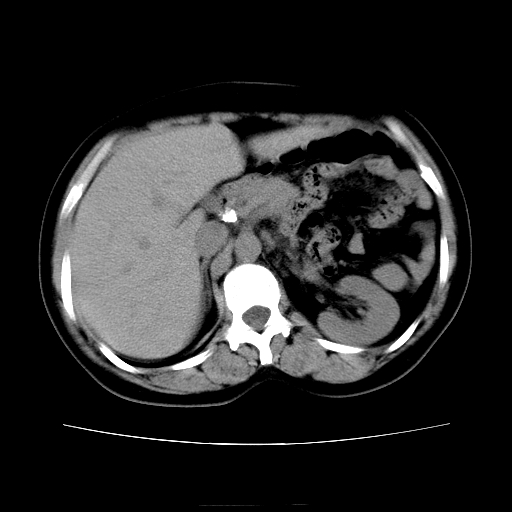

女45y多次(7次)碎石,结果不理想!曾碎石后尿出小碎石,仍腰痛,要求ct,其它不详.本人更倾向于钙化斑!无肾实质破坏,积水等提示集合系统无梗阻.另外腹腔多处钙化.是否结核后改变!谢谢赐教!

1)双肾结石。2)脾脏钙化灶。3)腹膜后多发淋巴结钙化。

尿路结石与腹部淋巴结钙化共存,建议v尿路造影检查,免得钙化灶冤枉为结石受罚。

考虑双肾结石,肾脏实质无破坏表现,没有结核病史,不考虑肾结核,